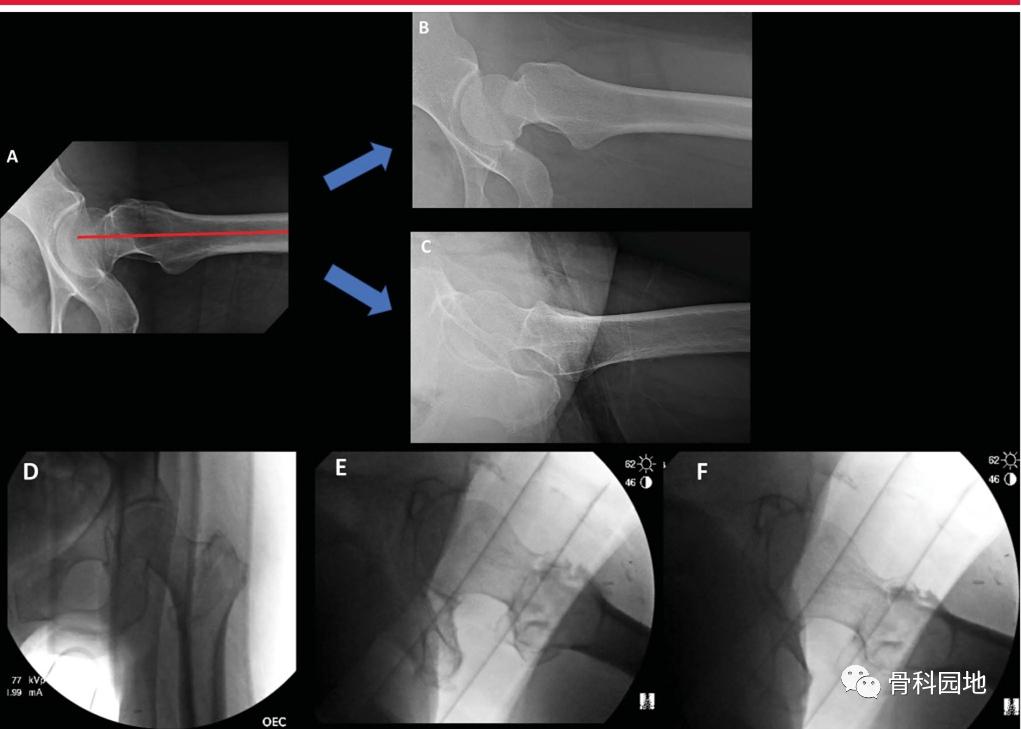

专门的髋部x线片是评估骨折形态的必要条件。虽然大转子尖端与股骨头中心之间的关系通常是共面的,但正位骨盆或对侧髋关节x线片可以帮助评估天然解剖结构和潜在的髋外翻(coxa valga )或者髋内翻(coxa vara) (下图A正常颈干角,B髋外翻,C髋内翻)

内旋牵引x线片在术前计划中特别有用。特别地,Khurana等人证实,内旋牵引x线片显著提高了股骨近端骨折分类的诊断准确性、可信度和观察者间的一致性。此外,术前牵引x线片可以帮助外科医生确定闭合复位动作何时可能成功(图2)。

逆转子间骨折在复位和植入方面存在特别的挑战。需区分高能和低能粗隆部骨折,因为这些骨折的“表现”不同(下图)。虽然低能骨折可以在骨折手术台上通过闭合复位成功治疗,但高能骨折通常需要经皮或开放复位技术。

左侧髋关节侧位透视图显示尽管骨折手术台上有足够的牵引和旋转,骨折碎片仍有较大的移位。

为了评估骨折固定期间的透视视图,必须了解完整股骨的近端股骨关系,以及它们如何随透视光束位置、腿部位置和正常解剖变异而变化。股骨近端图像显示股骨粗隆尖与股骨头中心的标准关系,当股骨近端向外旋转时,股骨颈轴角度增加,股骨颈似乎变短(下图)。

x线片显示同一髋从内旋(IR)到外旋(ER)的AP透视图像。注意髋关节从IR到ER的距骨轮廓的变化。当颈干角从屈曲/IR到屈曲/外旋时,注意颈干角角度的外观。

同样,髋关节屈伸可以显著改变颈轴角度的透视图。在Bhashyam等人的研究中,髋关节屈伸和旋转对NSA的测量有协同效应,当髋关节屈伸在中立位10°以内时,测量误差最小。因为受影响的髋关节倾向于屈曲和内旋,这会给人内翻增加的错觉。

术中髋关节侧位透视对复位和植入物的评估。A,侧位图像最适合植入物,显示股骨头、股骨颈和股骨轴共线。B,同一髋关节内旋侧位片。C,同一髋的外旋转侧位图像,是评估前内侧皮质支撑和髋粗隆部骨折复位的最佳选择。D - F,术中透视图像获得骨折台上仰卧位,显示AP (D)、侧位植入物(E)和侧位复位(F)视图